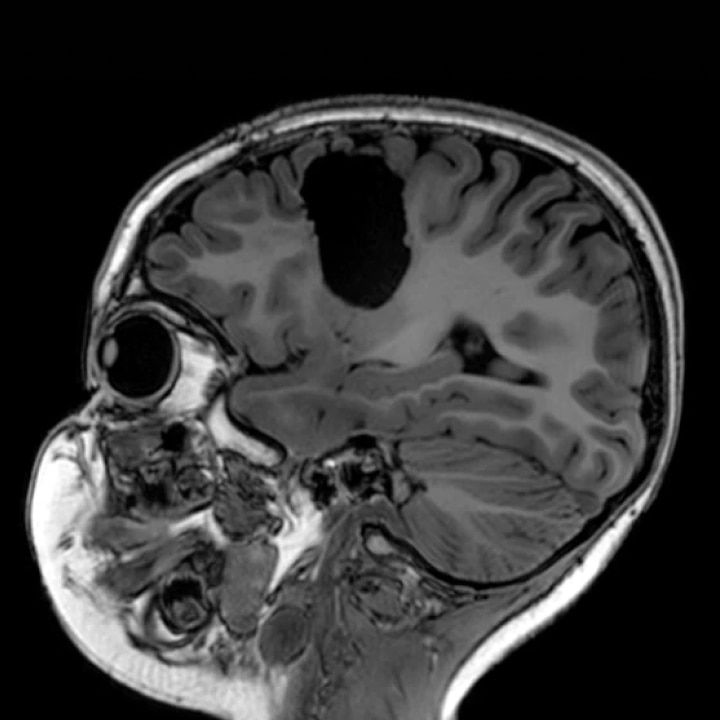

Our boldest ideas yet

Meet our next-generation SIGNA MRI scanners & solutions

SIGNA MRI Scanners

Our 1.5T, 3T, PET/MR and 7T scanners deliver the latest in imaging innovation with AIR Recon DL, and AIR Coils.